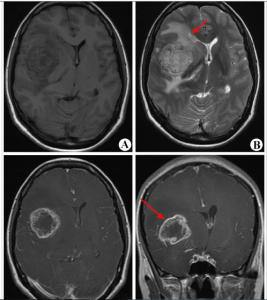

神經影像學特點

病程呈瀰漫性浸潤生長,範圍廣泛,邊界不清,受累區域的腦組織腫脹,溝變淺或消失,腦室變小。病變早期占位效應常不明顯,中線結構常沒有移位。病變中、晚期可表現出占位效應,若病變偏一側,占位效應徵象可較早出現。腫瘤細胞多侵犯大腦半球2個或2個以上的部位,皮層及皮層下白質均可受累。